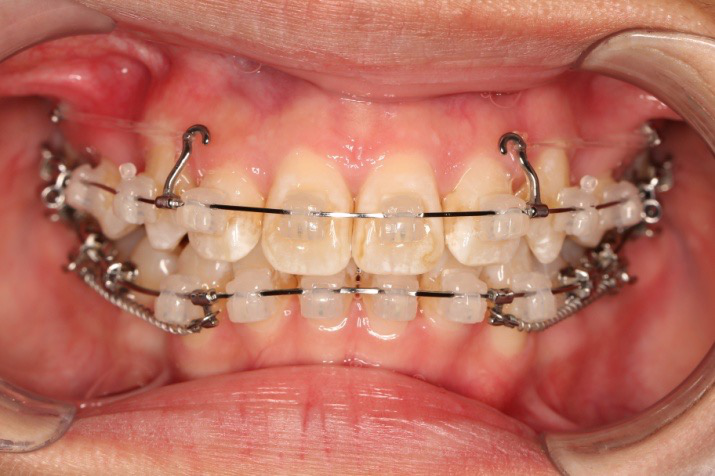

1.第0个月:2016.10.31 ◆ 初戴,0.013cu-niti

2.第2.5个月:2017.1.13 ◆ 上颌加TPA,植入1312-08种植钉,上下0.16cu-niti

2016.10.31  初戴,0.013cu-niti2017.1.13  上颌加TPA,U56间斜形植入韩国庆北1312-08种植钉,上下0.16cu-niti

2017.02.16  上下0.014*25 cu-niti,50g 拉尖牙远中

2018.11.14  术后磨牙尖牙I类关系,中线齐,覆合,覆盖正常